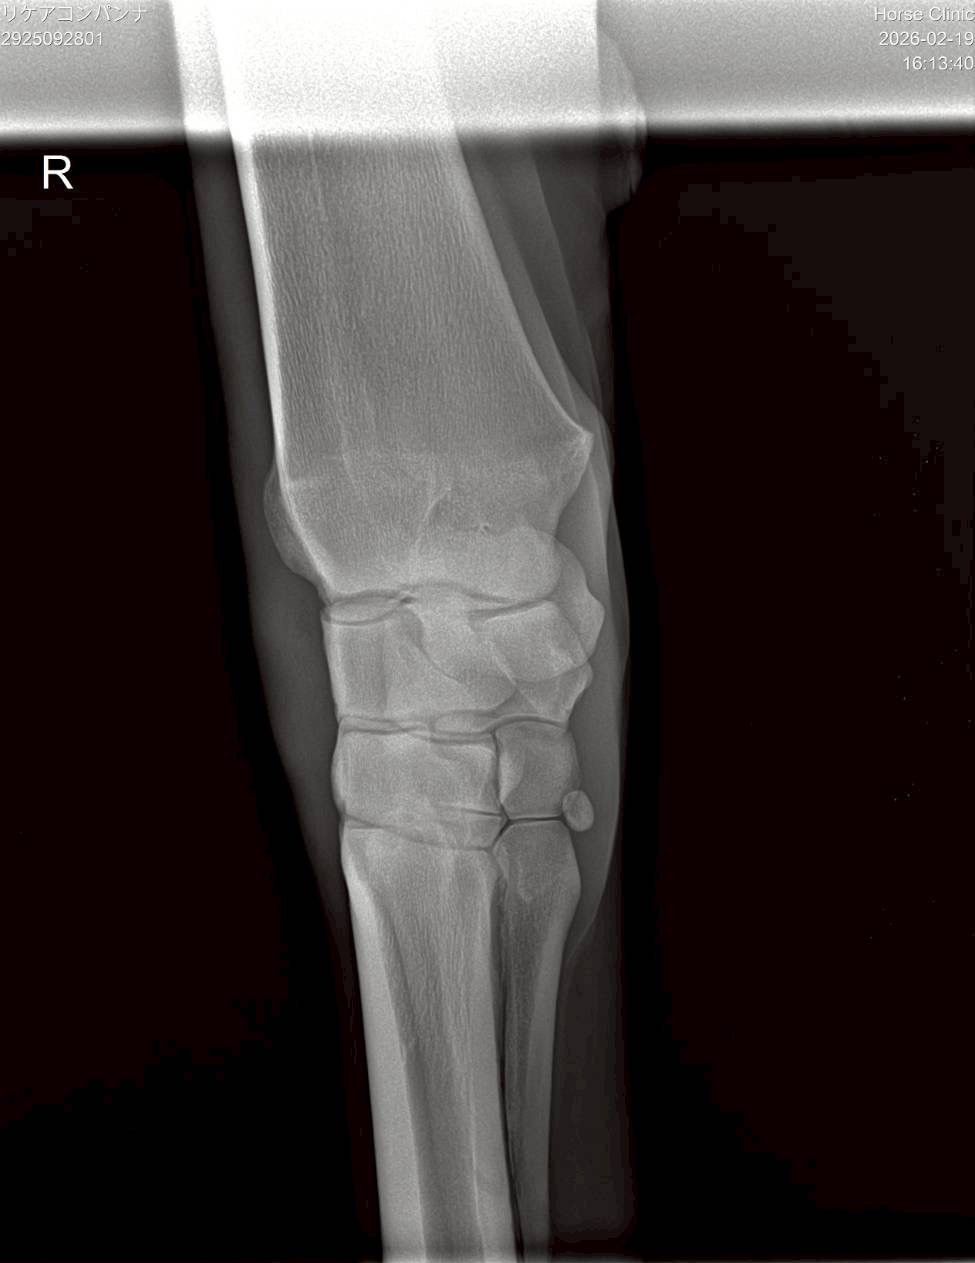

昨年8月の前走で右前肢の橈骨遠位端骨折を発症してしまいました。見舞金9号(競走中6カ月)を受給したうえ、手術は受けていません。休養を取って立ち上げ、現在は周回コースでキャンター2500mを18―18で、週1回は坂路で1本15―15を消化中。馬体重は2月16日の測定で500㎏です。

※2025年8月19日の競走で右前肢橈骨遠位端骨折を発症。事故見舞金9号(競走中の事故により事故発生の日から6ヵ月以上中央競馬の競走に出走できなくなった場合)を受給しています。